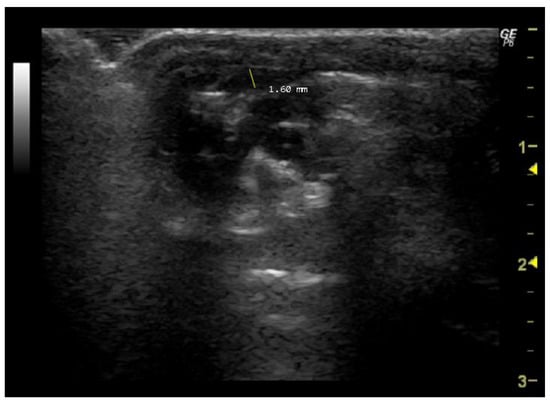

- How to measure pulmonary artery diameter

4.1.3. Apical View